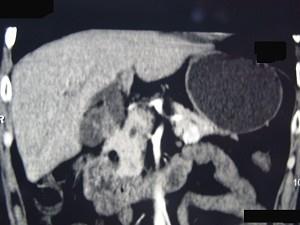

问题 男性,57岁,1年前无明显诱因反复出现嗜睡及发作性神志不清,进食糖水或甜品后症状即缓解,腹部CT检查如下图,最佳的诊断是 ( )

选项 A、胃泌素瘤 B、舒血管活性肽瘤 C、胰岛细胞瘤 D、胰腺转移瘤 E、胰腺癌

答案 C